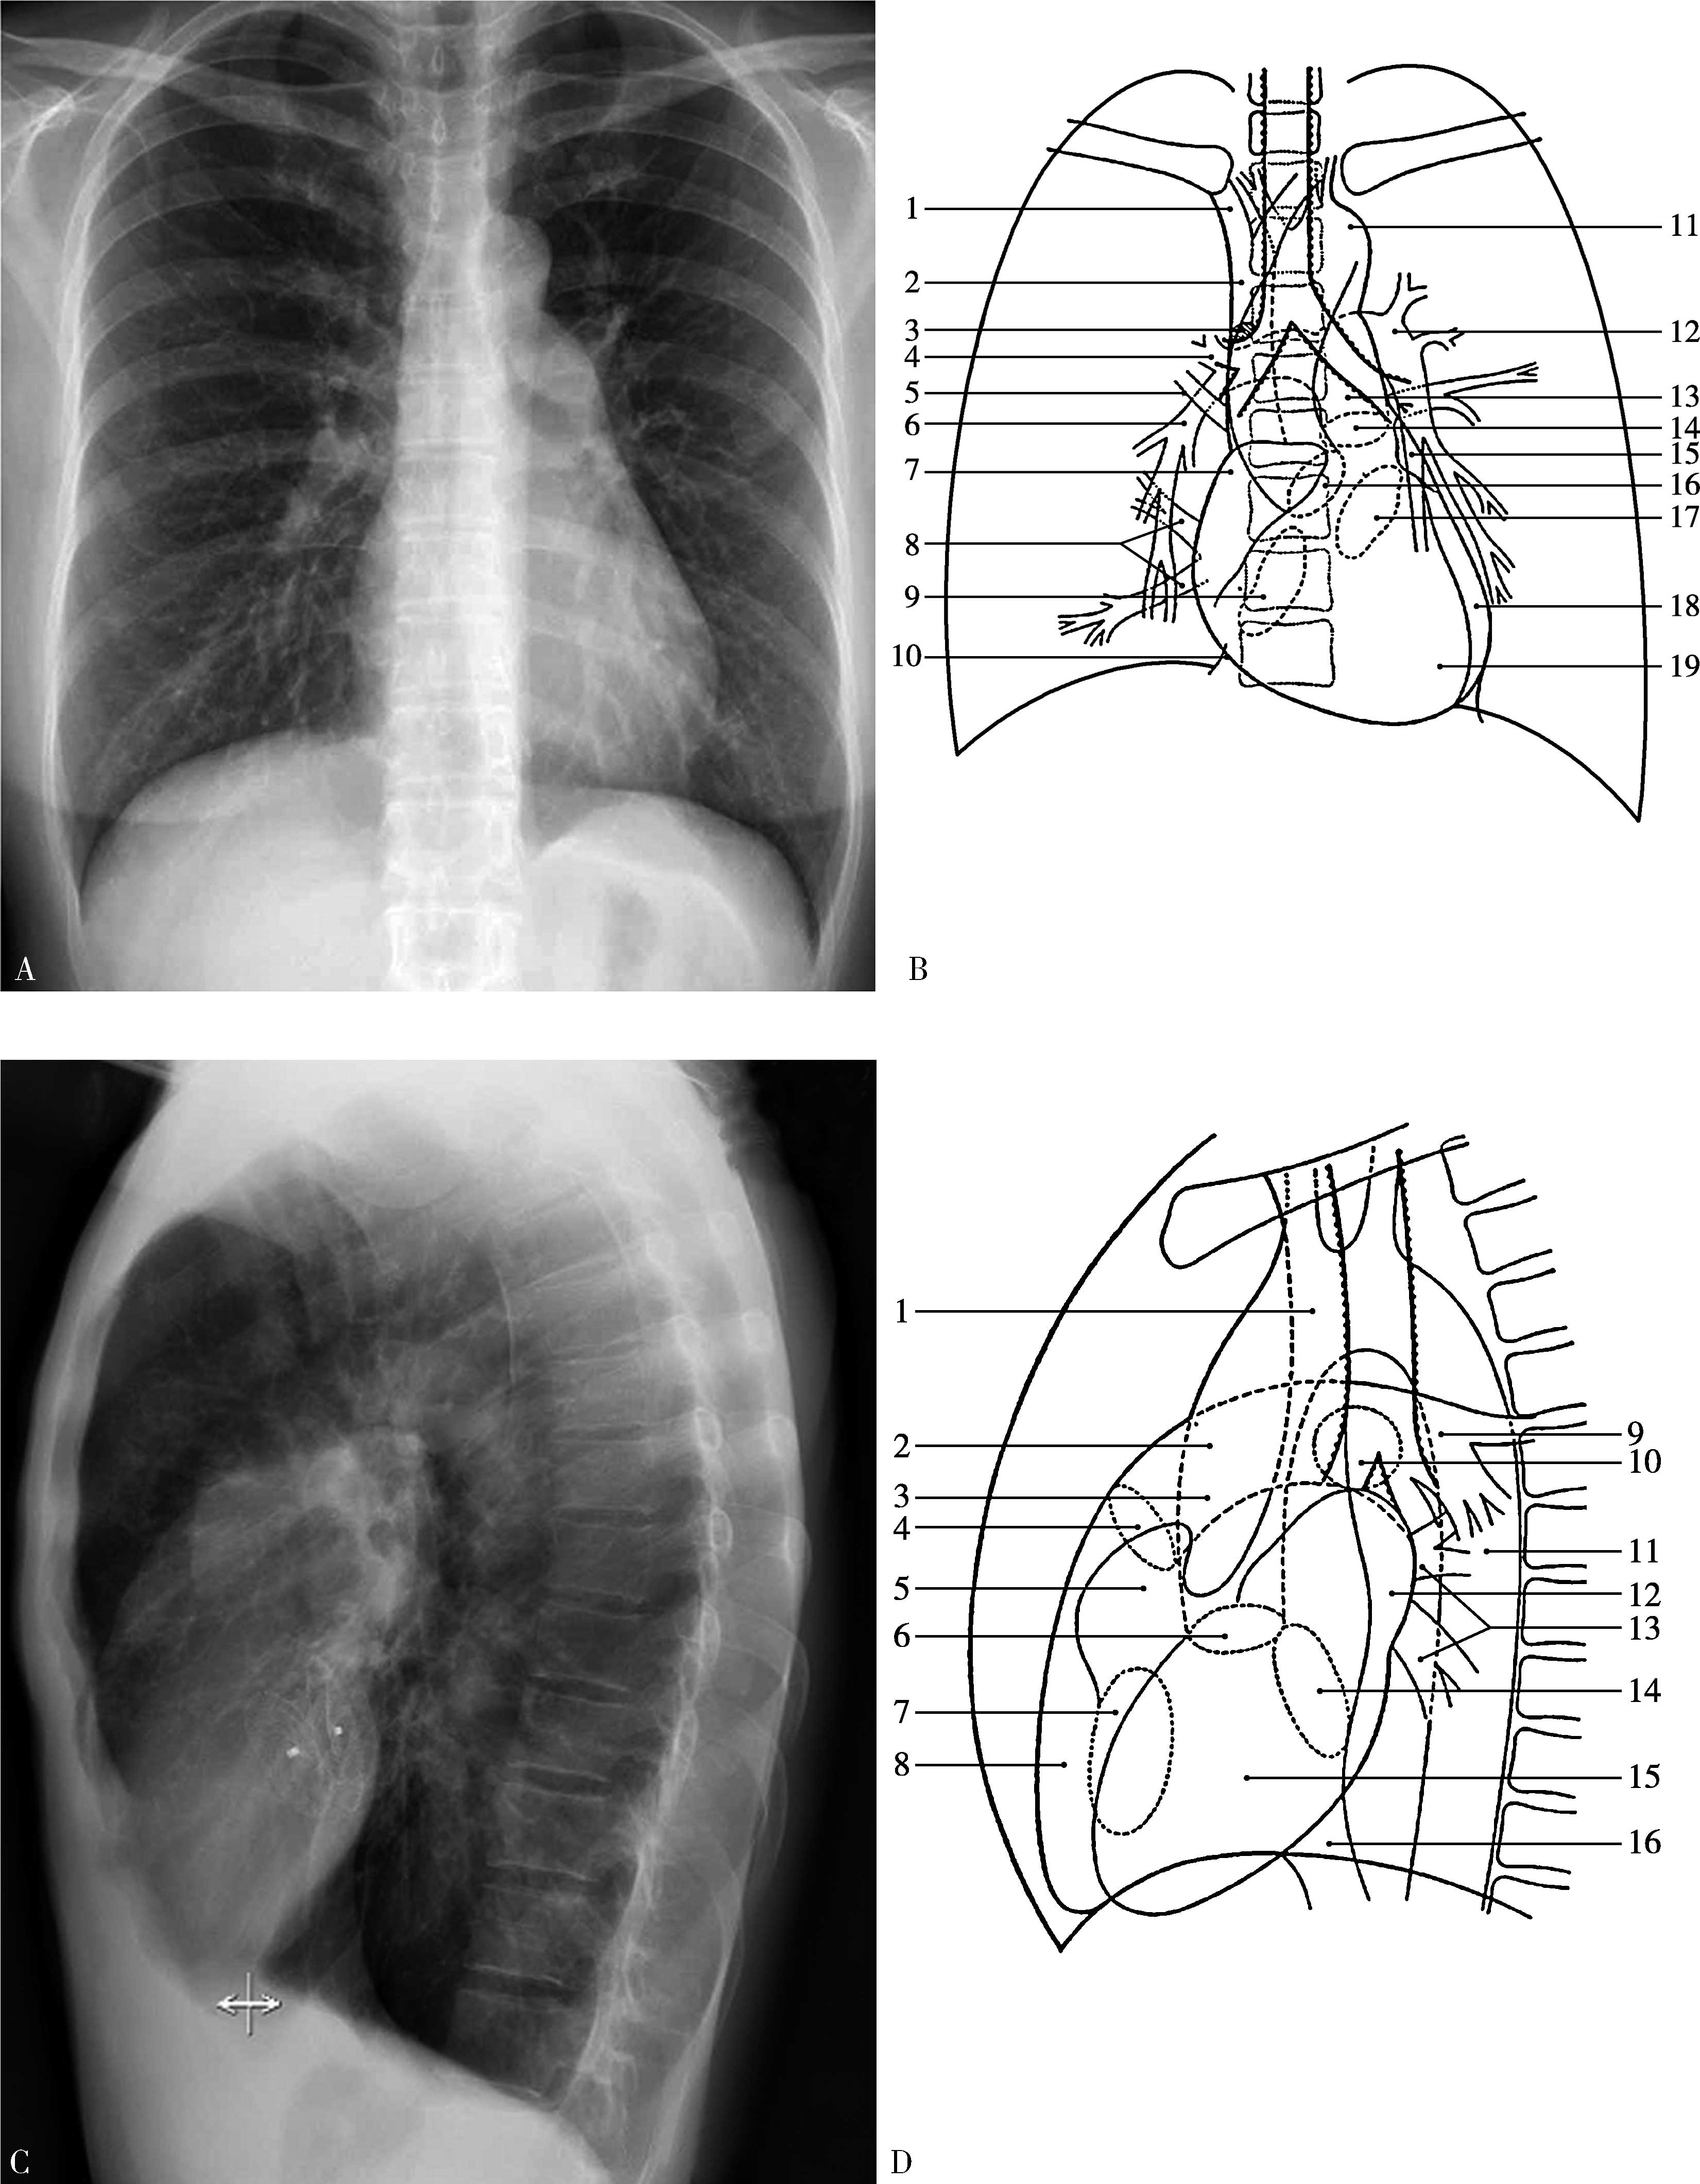

图7-1-1 心脏远达及左侧位X线片及模式图

A.心脏远达X线片,B.胸部正位X线片模式图:1右无名静脉;2上腔静脉;3奇静脉;4右上肺动脉;5右上肺静脉;6右下肺动脉;7右心房;8右下肺静脉;9三尖瓣口;10下腔静脉;11主动脉弓;12左肺动脉;13主肺动脉;14肺动脉瓣口;15左心房耳部;16主动脉瓣口;17二尖瓣口;18左心室;19右心室,C.心脏左侧位X线片,D.胸部左侧位模式图:1上腔静脉;2主肺动脉;3升主动脉;4肺动脉瓣口;5右心房耳部;6主动脉瓣口;7三尖瓣口;8右心室;9左肺动脉;10右肺动脉;11降主动脉;12左心房;13肺静脉;14二尖瓣口;15左心室;16下腔静脉